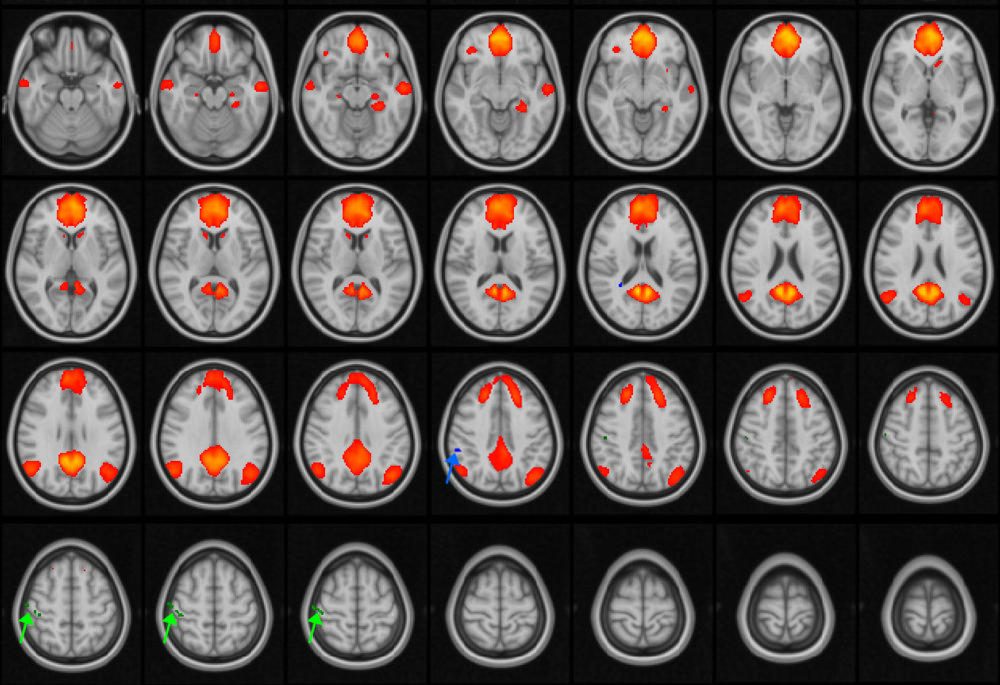

All patients and control group participants were scanned using resting-state fMRI while doing nothing but keeping their eyes open during the imaging process. The fMRI allowed researchers to evaluate the default mode network by identifying which areas of the brain activated during imaging.

“When certain areas of the brain get active, blood flow increases in those areas,” Dr. Johnson said. “Using a data analysis technique, we’re able to create a map for each individual in the study that shows how activity was distributed in space and over time.”

Compared to controls, the researchers found no difference in the connectivity in the default mode network in patients who had experienced one or two concussions. In patients who had three to five concussions, the maps detected a disruption in the default mode network.

Figure 1. MRI images of the brain, with the default mode network (DMN) highlighted in orange/red. The DMN is active during periods of wakeful rest, when the mind is not focused on a particular task. The green and blue arrows point to areas of the network that are disrupted in adolescent patients with concussions.